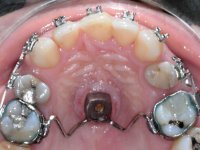

Tendo em conta a relação de Classe II molar e canina, o plano de tratamento contemplou a seguinte abordagem multidisciplinar:

1) Extracção do 2º pre-molar superior direito,

2) Tratamento ortodôntico com o objectivo de criar espaço entre as raízes e as coroas dos dentes 11 e 22,

3) Colocação de um implante no espaço criado na zona do 21 associada a uma regeneração óssea guiada da zona,